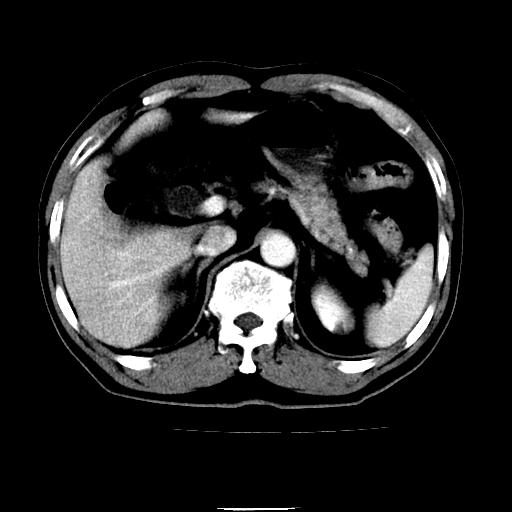

以下是引用chenqiong在2010-3-25 20:56:00的发言:[br]1、胆囊炎,胆囊息肉[br]2、肝内胆管及胆总管扩张,胆总管下端结石[br]3、十二指肠乳头旁憩室

以下是引用zxl51642在2010-3-26 10:47:00的发言:[br]胆囊炎,胆囊息肉,胆总管扩张,但未看到明显肿块,肝内胆管扩张不像恶性,炎性狭窄或阴性结石可能吧,建议mrcp,右肾小囊肿